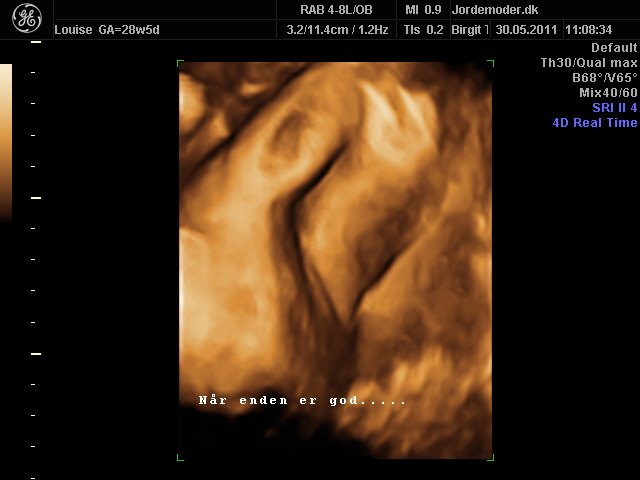

Her er billede af vores datter, som pænt viser hendes køn på begge billeder...

På 2d billedet ligger hun med maven ned af, og havde det været en dreng ville der ligesom falde noget ned der....

Det samme på 3d billedet, havde det været en dreng var der faldet noget ud der mellem bene....

Altså da vi var til 3d scanning tænkte jeg også hun sørne så stor ud dernede, også for stor til at være en pige... Men det er fordi de små piger har meget store skamlæber, så kan godt ligne en punk på scanningen... Var jeg dig ville jeg betale mig fra en scanning for at blive helt sikker i din sag....

Vedhæftede fotos (klik for at se i fuld størrelse)